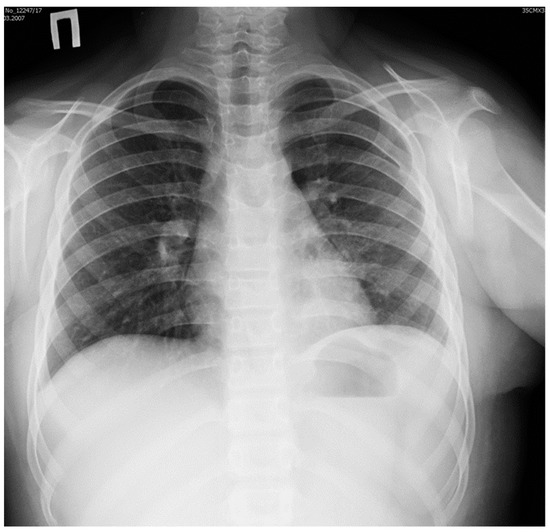

The postoperative course was without complications. Plain X-ray studies of the thorax obtained before the girl was discharged from the hospital confirmed the absence of infiltrates and pneumothorax (Figure 4).

Figure 4.

Plain X-ray image of the thorax obtained before discharge from hospital: normal appearance of left lung after resection of the pulmonary sequester.

The diaphragm was in normal position, and sinuses were free of fluid. Blood tests did not show any signs of inflammation.